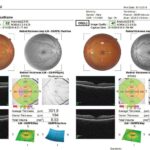

FOLLOW-UP SCAN

Easy retrieval, analysis, and comparison of past and current images for efficient eye care diagnosis

MORE DETAILS IN LESS TIME

A scanning speed of 50,000 A-scans/sec allows for faster tomography acquisition and produces clear, high-definition cross-sectional retinal images through a simple interface.